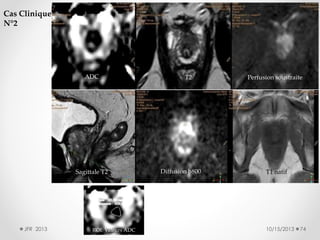

Cas Clinique

N°2

ADC

Sagittale T2

JFR 2013

ROI: Valeurs ADC

T2

Diffusion b800

Perfusion soustraite

T1 natif

10/15/2013